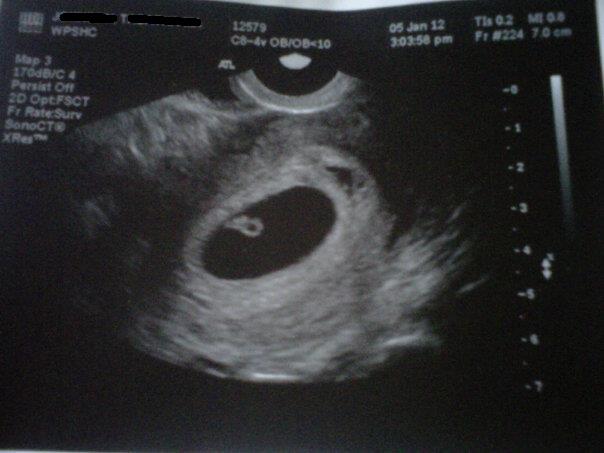

according to Ramzi Theory, the placement of the placenta in a 6-8 week ultrasound can help determine what GENDER the baby will be. Using Transvaginal ultrasounds you do not flip the image, but if it's abdominal you do. This is Transvaginal at 6w4d :)

Attachment 1212